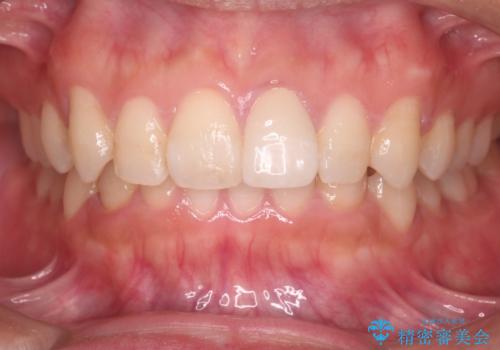

インビザラインにて治療を行うことで、前歯のがたつきが改善されました。

左上1番目の前歯はセラミックをご希望されたので、セラミックにて被せ物の治療を行いました。

とても綺麗な前歯になりました。